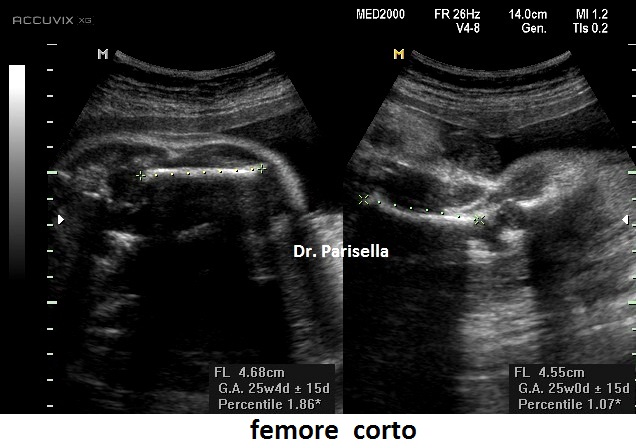

La condrodisplasia puntata rizomelica ha una prevalenza stimata in 1:100.000. E' caratterizzata da nanismo che colpisce soprattutto il tratto rizomelico ( femore e omero ), tipico aspetto del viso (ampio ponte nasale, epicanto, palato ogivale, orecchie esterne displasiche, micrognazia)  alterazioni vertebrali, cataratta, lesioni cutanee e grave ritardo mentale. Le alterazioni vertebrali consistono caratteristicamente in lesioni coronali dei corpivertebrali. La malattia è causata da un difetto del metabolismo dei perossisomi e viene trasmessa come carattere autosomico recessivo.

La Condrodisplasia Puntata legata all'X Dominante o Sindrome di Conradi-Hünermann può essere diagnosticata in epoca prenatale, di solito nel III trimestre. E' caratterizzata da bassa statura legata ad ipoplasia di omero e femore (l'omero è colpito principalmente), asimmetria degli arti, scoliosi, epifisi slargate con multipli foci iperecogeni, contratture articolari; segni presenti ma non evidenziabili all'ecografia sono l'eritroderma ittiosiforme lamellare e la cataratta, che può essere monolaterale. L'intelligenza è normale. La malattia colpisce prevalentemente le femmine ed è più grave o addirittura letale nei maschi. È trasmessa come carattere dominante legato all'X, dovuta a mutazioni nel gene EBP che codifica per un enzima coinvolto nel metabolismo del colesterolo.

La condrodisplasia puntata può essere diagnosticata ecograficamente in epoca prenatale, di solito negli stadi avanzati della gravidanza, ma la classificazione esatta richiede approfondimenti biochimici (ricerca di steroli anomali e acidi grassi a catena molto lunga) sui campioni di liquido amniotico.  La prognosi è molto variabile.